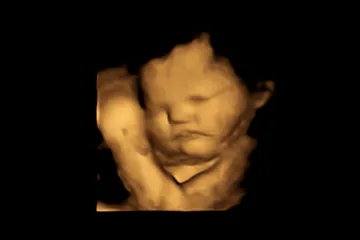

Z chutě kapusty se mračí už plody v děloze, zjistil výzkum

Pokud se vám při chuti kapusty zkřiví obličej, nejste sami. Vědci zjistili, že se to děje už v děloze nenarozeným dětem. Popsali to ve studii, podle níž je u dětí výraz podobný zamračení dvakrát pravděpodobnější, pokud ucítí kadeřávek, než když ochutnají mrkev.